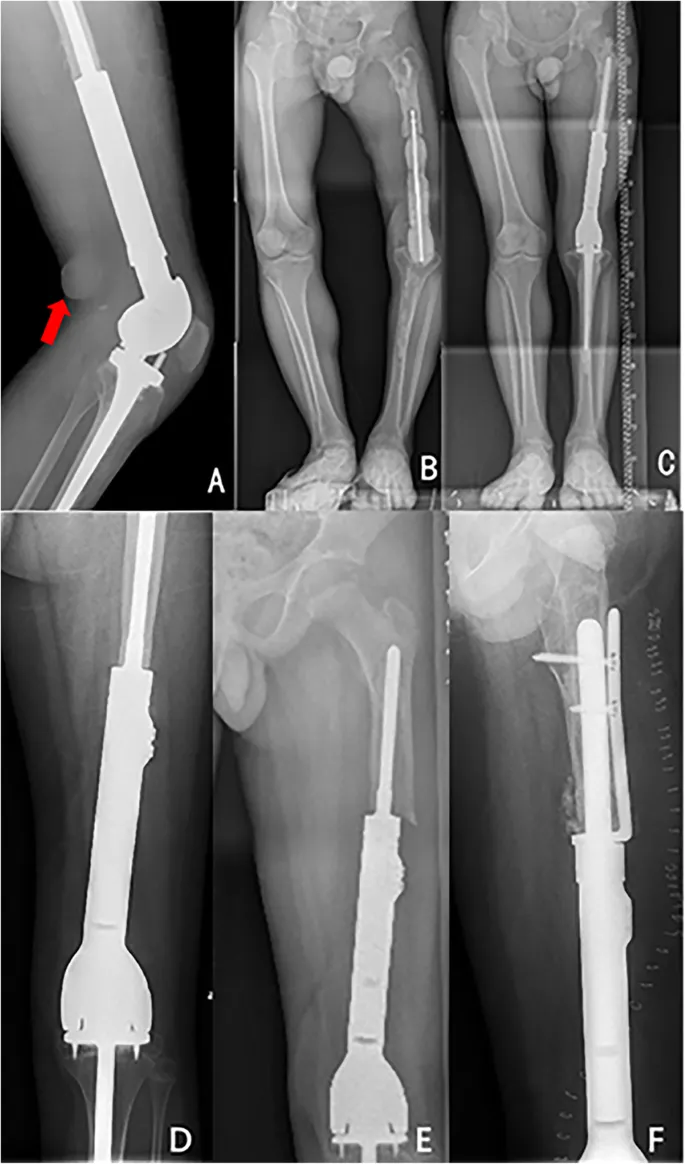

- Endoprosthetic Replacement: Most common; metallic implants (custom mega-prosthesis).

⭐ Distal femur is the most common site for endoprosthetic replacement in LSS, followed by proximal tibia.

- Implant Issues: Loosening, fracture, failure.